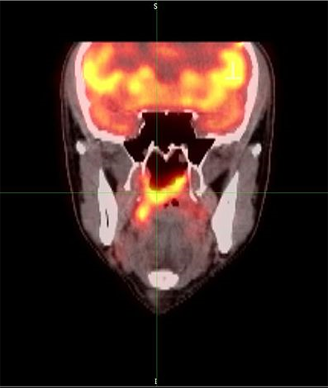

PET Scan of nasopharynx carcinoma; source: Sanko, Wikimedia Commons